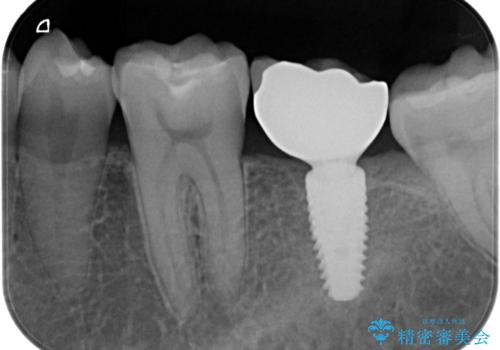

奥歯のインプラント

- 奥歯が割れたあと、他院で抜歯したところにインプラントを希望して来院。2回法で行いました。

奥歯を抜いたまま放置すると後方の歯が前に倒れこんでしまい、かみ合わせやその後の治療に支障がでます。早めに処置することをおすすめします。